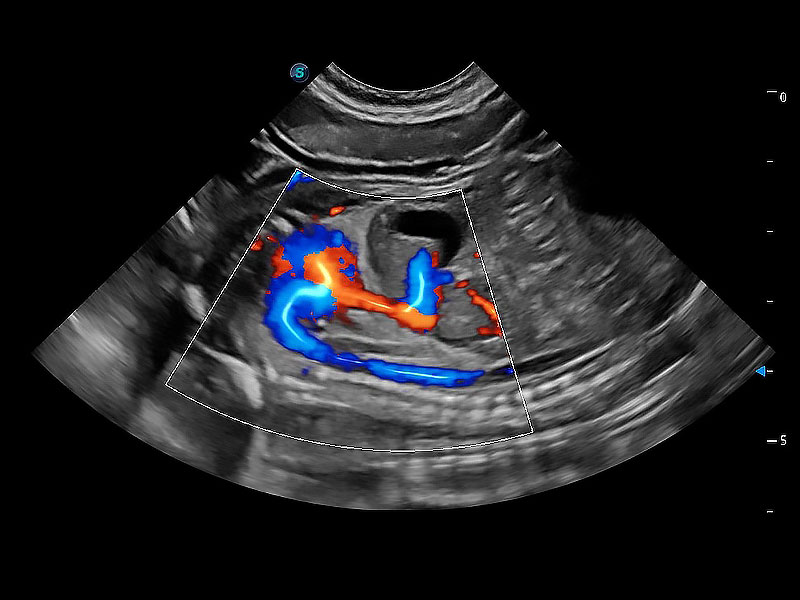

(犬)二腔心血流

(犬)四腔心MQA

• MQA 心肌定量分析

通过心肌识别技术与二维斑点追踪技术相结合,对心脏的超声图像进行量化分析。计算心肌17个节段的应变、应变率、速度、位移等,并通过牛眼图的形式进行呈现。